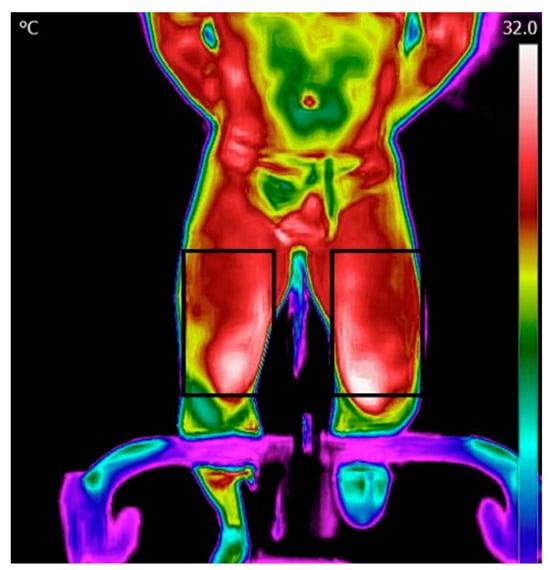

Thermal images of the upper (the chest and forehead in one image) and lower body (both thighs in one image) were captured at rest, before the test (after the warm-up), immediately after the test, and every 60 s during the 15 min recovery period. In each case, a picture of the legs, chest, and forehead was taken (Figure 1).

The images were taken freehand, without the use of a tripod. To maintain uniformity, images were taken at a fixed one-meter distance. The imaging procedure included images of the anterior torso (the chest and forehead) and each leg. The male participants were asked to remove their top clothing, while the female participants were requested to wear sports bras. The angle of the image was maintained at a constant value with the camera set parallel to the body of the participant (anterior view) while seated in an upright position. Each time, an image of the chest and forehead was followed by an image of the legs. Images were captured at rest, before the test (after the warm-up), immediately after the test, and every 60 s during the 15 min recovery period (Figure 1).

Figure 1. Test procedure and example of an image obtained from the thighs over the course of the experiment. Thermal images were taken at baseline (before the Wingate test - WanT), immediately after the test, and every 60 s during the 15 min recovery period. The increase in surface temperature can be seen via the change in the color bar on the left.

Figure 2. Regions of interest for the legs.